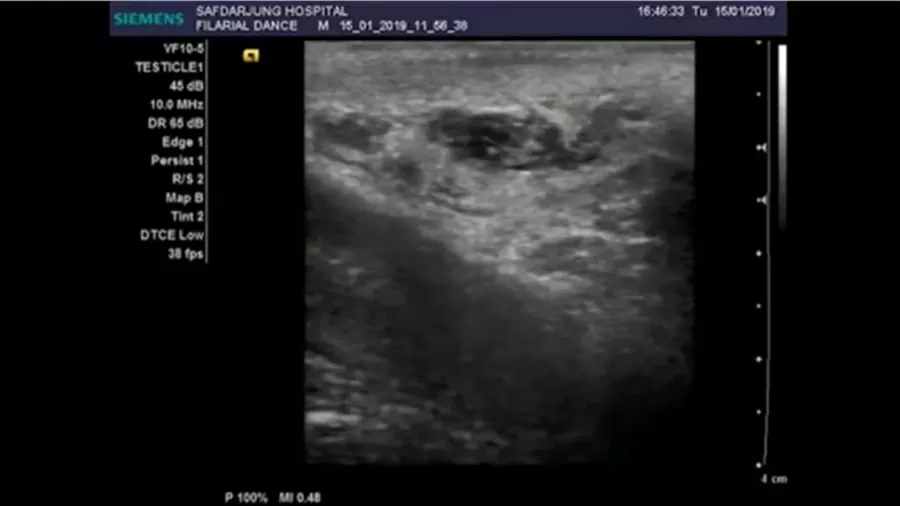

“No exame de ultrassom, estruturas em movimento foram vistas dentro de um canal linfático dilatado [tubos finos que transportam fluido e glóbulos brancos no escroto]”, descreveram os médicos no estudo de caso publicado na última edição do New England Journal of Medicine.

Ultrassonografias revelaram que o indiano tinha os vermes “dançando” na sua região inferior e ele foi diagnosticado com uma filariose linfática, também conhecida como elefantíase.

A “dança” dos vermes é conhecida como “sinal da dança filarial”, causada pelas “ondulações de vermes vivos que migraram para os canais linfáticos, o que causa dilatação e disfunção”, segundo o estudo.